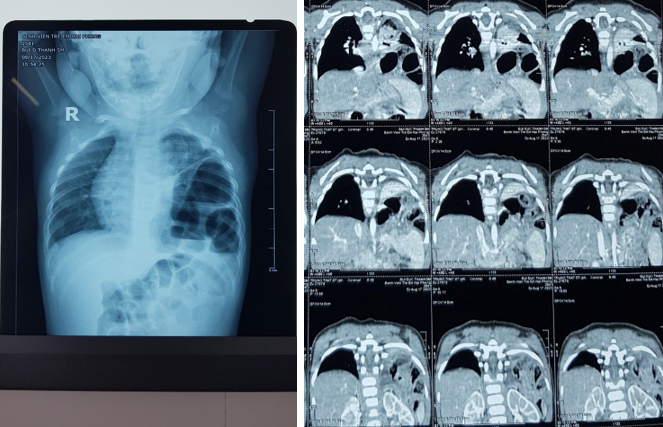

Hình ảnh Xquang và cắt lớp vi tính có nhiều quai ruột trong lồng ngực bên trái

Ngay lập tức cháu được khám và chỉ định các xét nghiệm cần thiết, qua đó phát hiện tình trạng các quai ruột non, ruột già chui từ ổ bụng lên lồng ngực qua 1 lỗ thủng bẩm sinh ở vùng bên trái của cơ hoành, gây nên tình trạng tắc ruột, đồng thời phổi bên trái bị đè ép làm giảm nặng chức năng trao đổi khí. Trẻ được chỉ định mổ nội soi điều trị do kíp mổ khoa Ngoại tổng hợp và kíp gây mê khoa gây mê hồi tỉnh bệnh viện Trẻ em Hải Phòng thực hiện.